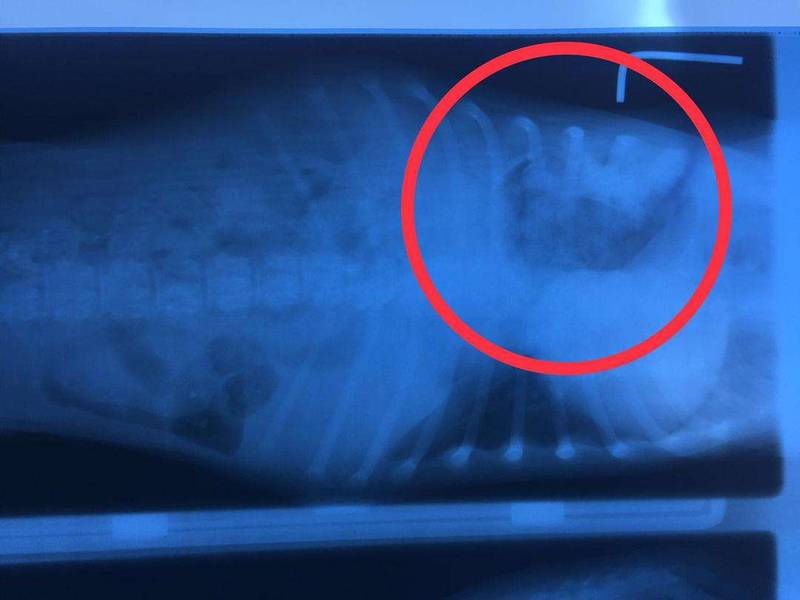

دامپزشکان با کمک رادیولوژی حیوانات میتوانند دید بهتری نسبت به مشکلات حیوانات داشته باشند و با کمک این دید درمان های تأثیرگذارتری را برای حیوانات خانگی در نظر میگیرند. از جمله دغدغههای مهمی که صاحبان حیوانات خانگی دچار آن میشوند،یکی از نکاتی که در زمان انجام رادیولوژی و mri حیوانات خانگی به ویژه سگ ها و پرندگان باید به آن دقت کرد این است که رادیولوژی به تخصص نیاز دارد و ممکن است هر دامپزشکی نتواند این کار را انجام میدهد. زیرا در امور تشخیصی و درمانی برای حیوانات نیز مانند افراد به تخصص کافی نیاز میباشد.